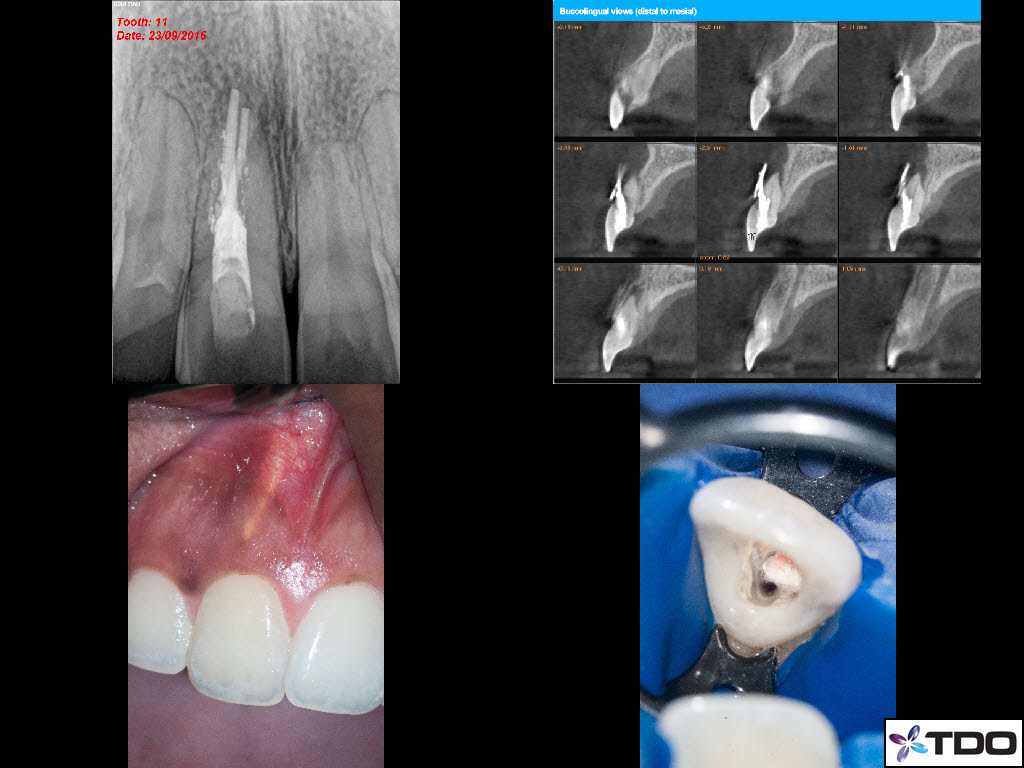

23 YF presented with pain and clinical signs of GP inside the buccal aspect of the gingiva around tooth #11 (FDI). The scan shows the buccal perforation with two GP points and an apical finding. Initially we removed all GP fragments internally and repaired the internal aspect of the perforation with SDR and interim CaOH was placed into the true canal. Second visit, the patient was asymptomatic and the surgical phase involved repairing the perforation defect with Geristore. The RCT was then completed and the access was closed with resin. Patient was very happy with the aesthetics at the follow-up and no- probing was evident at the perforation site through the buccal marginal gingiva. I hope this turns out well long-term.